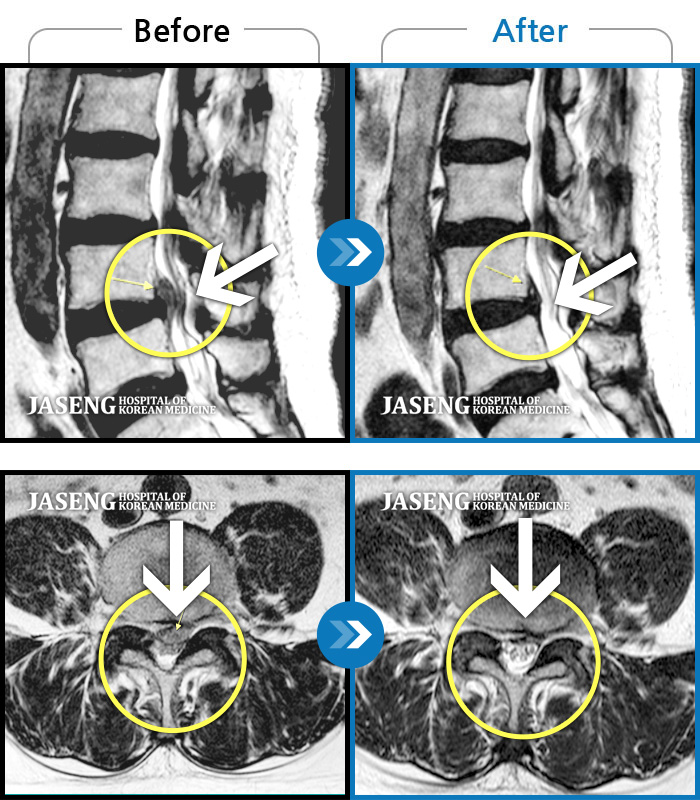

Before

After

환자에게 사전 동의를 받아 동일 조건에서 촬영되었습니다.

개인에 따라 치료 후 부작용이 발생할 수 있으니 의료진과 상담 후 치료를 진행하시기 바랍니다.

허리통증, 왼쪽 다리 통증 및 근력 저하

허리디스크로 인한 방사통